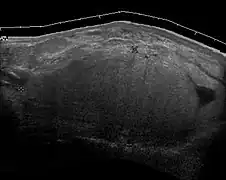

Medical ultrasonography of a lipoma in the thenar eminence: It is hyperechoic compared to adjacent muscle, and relatively well-defined, with miniature hyperechoic lines.[23]